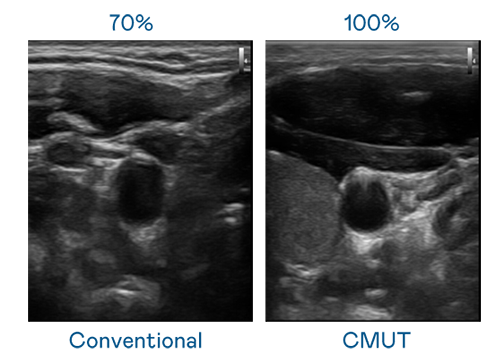

CMUT 技术是一种用电容式微机电元件来产生超音波讯号的技术。与传统 PZT 压电式技术相比,CMUT 频宽增加 30%,更宽频的超音波讯号让影像解析度大幅提升,是实现高影像品质医疗超音波扫描、促进精准医疗发展的关键技术。

超音波影像的解析度高低,首先取决于探头能发出的讯号频宽。Z6尊龙·凯时 CMUT 可提供高清晰的超音波讯号,提供高频宽、高灵敏度、影像纹理细节更高的超音波影像,协助医护人员缩短影像判读时间及利用精准的医疗影像进行诊断。